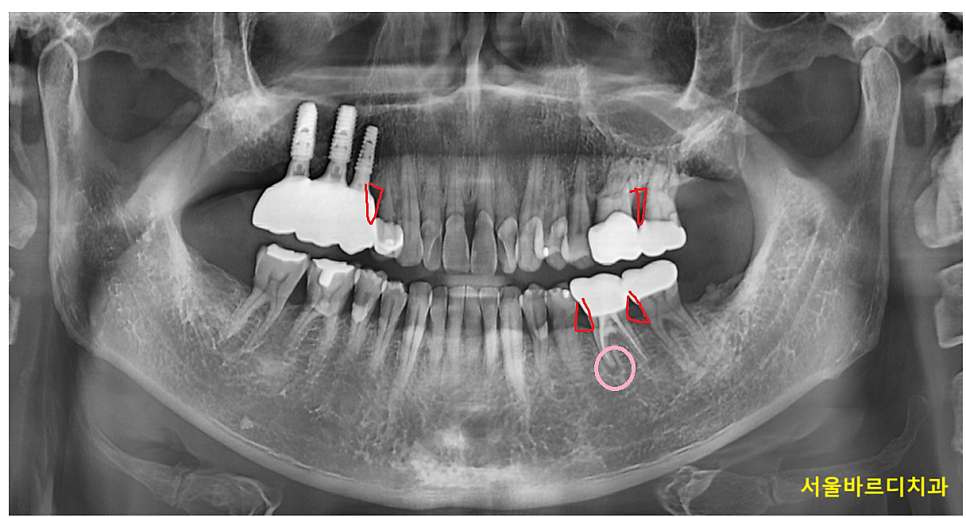

240127 풍치와 뿌리 끝 염증이 동시에 있는 환자분

이 경우 겉으로는 멀쩡해 보여도 내부는 심각한 상태일 수 있죠.

두번째로는 풍치일 수 있습니다.

단순한 염증이 아닌 잇몸 뼈를 녹이고 고름이 차는 경우입니다.

풍치와 뿌리 끝 염증이 동시에 있을 수도 있습니다.